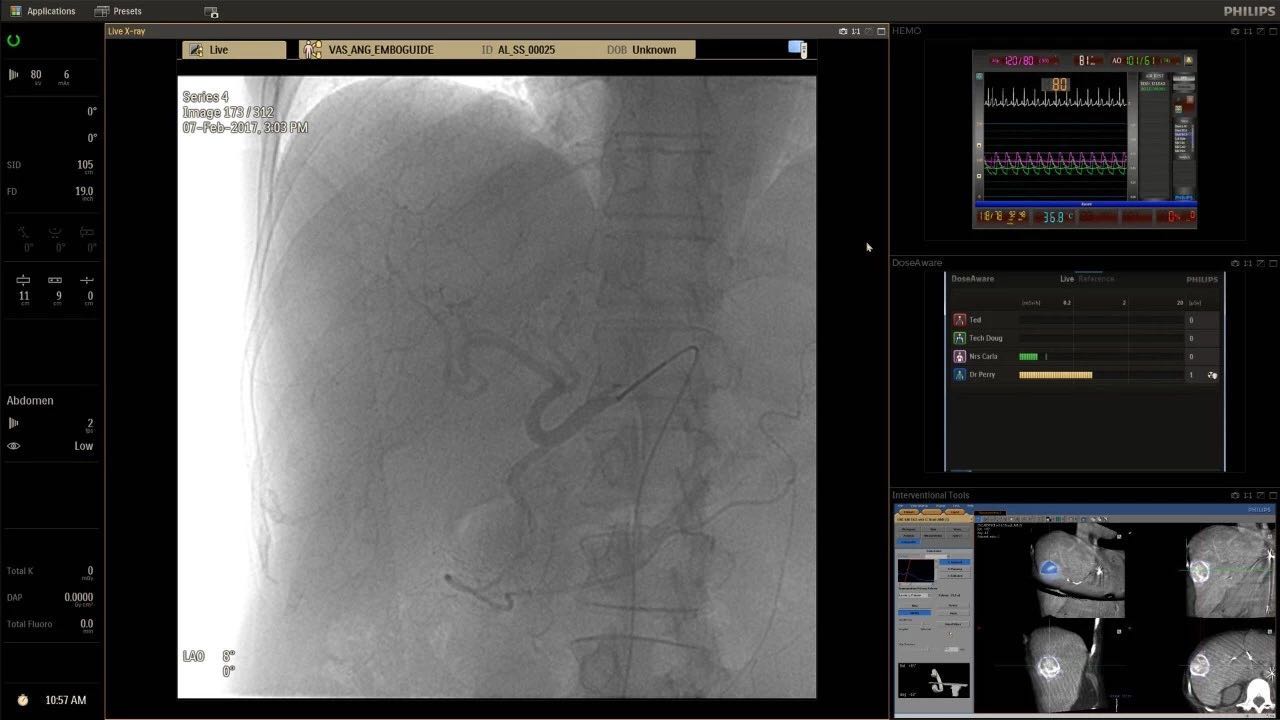

在日益復(fù)雜的干預(yù)期間,臨床醫(yī)生需要快速、輕松地可視化關(guān)鍵解剖結(jié)構(gòu)并確定手術(shù)過程中患者的變化。2019年1月17日,飛利浦宣布推出采用FlexArm的Azurion 7 C20,旨在提高圖像引導(dǎo)程序的定位靈活性。

帶有FlexArm的Azurion 7 C20 包含一系列創(chuàng)新技術(shù),使臨床醫(yī)生可以更輕松地在整個(gè)患者身上進(jìn)行二維和三維成像。當(dāng)臨床醫(yī)生移動系統(tǒng)時(shí),圖像光束自動保持與患者的對準(zhǔn),允許更一致的可視化并使他們能夠?qū)⒆⒁饬性谥委熒稀?/span>

可通過微創(chuàng)手術(shù)治療的疾病的范圍和復(fù)雜性繼續(xù)擴(kuò)大。相應(yīng)地,程序本身也變得更加復(fù)雜,需要來自不同學(xué)科的更多醫(yī)生在患者的桌邊,以高度協(xié)調(diào)的方式一起工作。因此,臨床團(tuán)隊(duì)需要在高度受限的環(huán)境中執(zhí)行越來越具有挑戰(zhàn)性的程序。

飛利浦表示,采用FlexArm設(shè)計(jì)的Azurion 7 C20可提供卓越的靈活性和直觀的控制。該系統(tǒng)由智能運(yùn)動引擎驅(qū)動,可在八個(gè)不同的軸上移動,所有這些軸均由其單個(gè)“Axsys”控制器控制。臨床醫(yī)生的模擬測試表明,該系統(tǒng)有可能顯著減少患者,工作人員和設(shè)備的重新定位,從而改善微創(chuàng)手術(shù)的可及性,包括通過患者手腕進(jìn)入身體的手術(shù)(橈動脈入路),并降低患者的風(fēng)險(xiǎn)。無意中拔出電線和管子,以及節(jié)省大量時(shí)間。該系統(tǒng)非常適合混合手術(shù)室(OR),可滿足一個(gè)房間內(nèi)的多種專業(yè)需求,例如手術(shù)和血管內(nèi)手術(shù)的組合。

FlexArm在不少于8軸的情況下旋轉(zhuǎn),從而創(chuàng)建幾乎無限的靈活性來執(zhí)行成像,從頭部到腳部在左側(cè)和右側(cè)進(jìn)行2D和3D可視化。圖像光束保持與患者對齊,允許在旋轉(zhuǎn)或角度期間更好地可視化解剖結(jié)構(gòu)。使用Axsys運(yùn)動控制系統(tǒng)輕松操作支架。